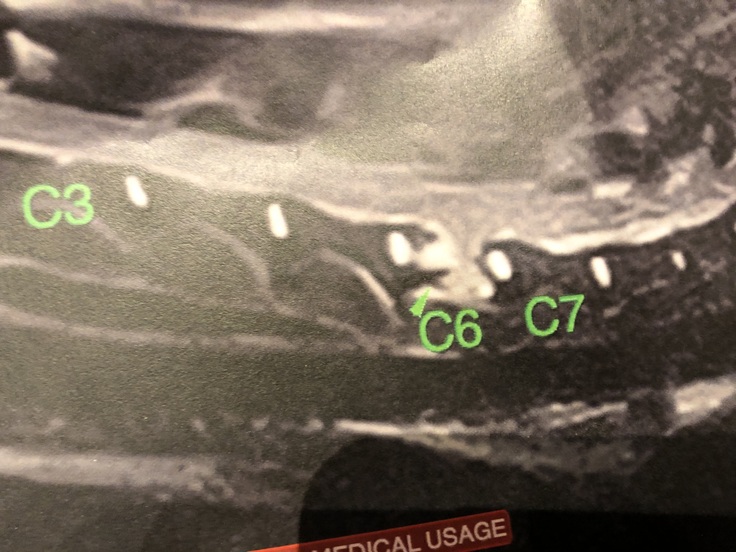

MRI検査で、頚椎6番の骨が、腫瘍に侵されてしまい、骨に穴が空き

そこから、腫瘍があふれ出てしまい。神経を圧追、神経麻痺を引き起こして居ました。

C6の滲んで見えるのが腫瘍です かなり大きいです

岐阜大学動物病院にて、頚椎に出来た、腫瘍を小さくする為に

放射線治療にて対応して頂きました。